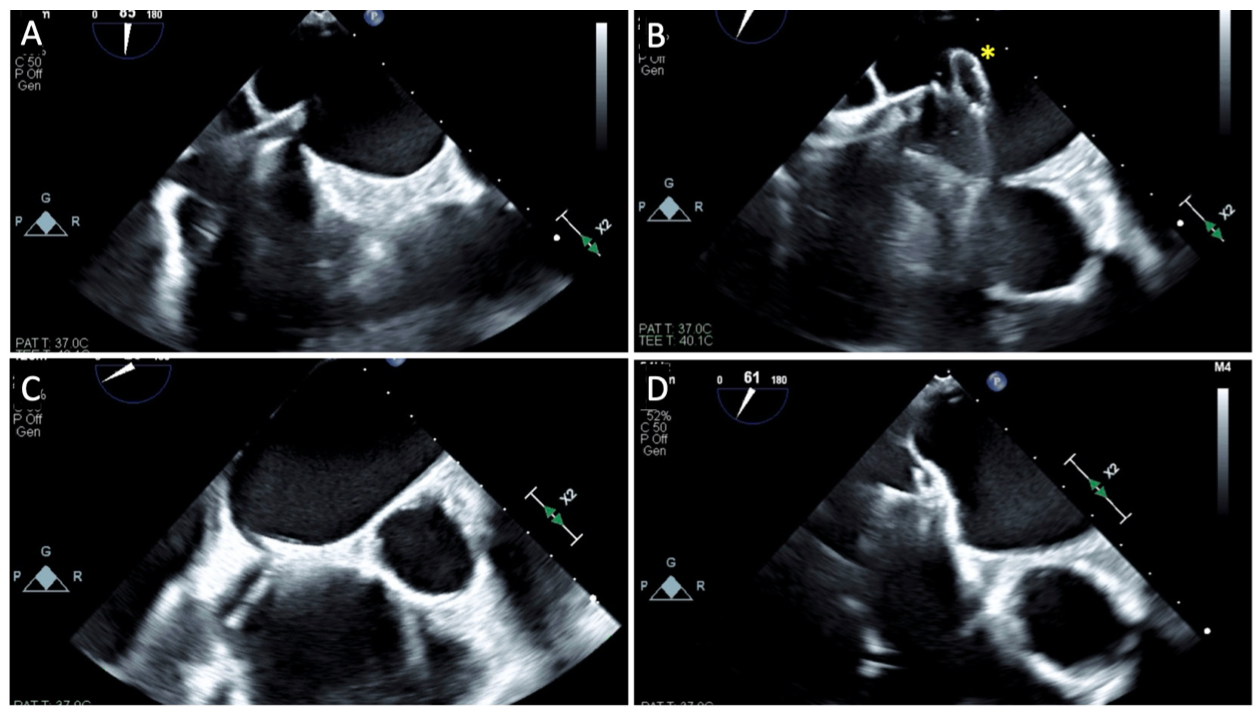

iASD closure via MitraClip SGC guide. After deployment of the last MitraClip, the clip delivery system (CDS) is removed in standard fashion leaving behind the 22-Fr SGC in the left atrium (Figure 1A). Next the Torqvue sheath (Abbott Vascular) with dilator (appropriately flushed and assembled) are advanced through the SGC valve in entirety (Figure 2A and 2B). At this point, the distal end of the Torqvue sheath remains within the SGC by 20 centimeters. The Torqvue dilator is removed and the sheath is aspirated and flushed in standard fashion and hemostasis achieved either by attaching a syringe or stopcock. On the back table, the selected occluder device is de-aired, flushed, prepped, and loaded per standard manufacturer specifications. The loading tube is then connected to the Torqvue sheath (in a fluid-to-fluid manner) and the Amplatzer cable is advanced allowing the collapsed occluder device to advance from within the loader and into the sheath (Figure 2C and 2D). However, given the discrepant lengths (Figure 3), when the occluder cable is advanced as far as allowable, the device has exited the Torqvue but remains constrained within the distal end MitraClip SGC. At this stage, on the backend, the occluder lock is disengaged and removed, next the loading tube (along with its Y connector) is disassembled and removed (Figure 2E). At this step, it is important to keep the proximal end of the Torqvue sheath below the level of the patient’s heart to prevent air entrainment. Next, the loading tube is disconnected from the Y connector followed by immediate advancement of the Y connector alone over the delivery cable to connect with the proximal end of the delivery sheath (Figure 2F). Hemostasis has now been re-achieved. By removing the loading tube, there is now sufficient cable length to advance the occluder beyond the distal end of the MitraClip SGC. The cable is advanced until the left atrial disc is deployed within the left atrium (Figure 2G and Figure 1B). The entire system is retracted until the left atrial disc is flush against the interatrial septum (Figure 1C). Next, the MitraClip SGC is withdrawn as the right atrial disc is formed (Figure 1D). Once appropriate positioning is confirmed, the delivery cable can be counterclockwise rotated per standard fashion until the threaded insert disengages and the device is fully deployed. The MitraClip SGC is now removed and femoral venotomy secured.